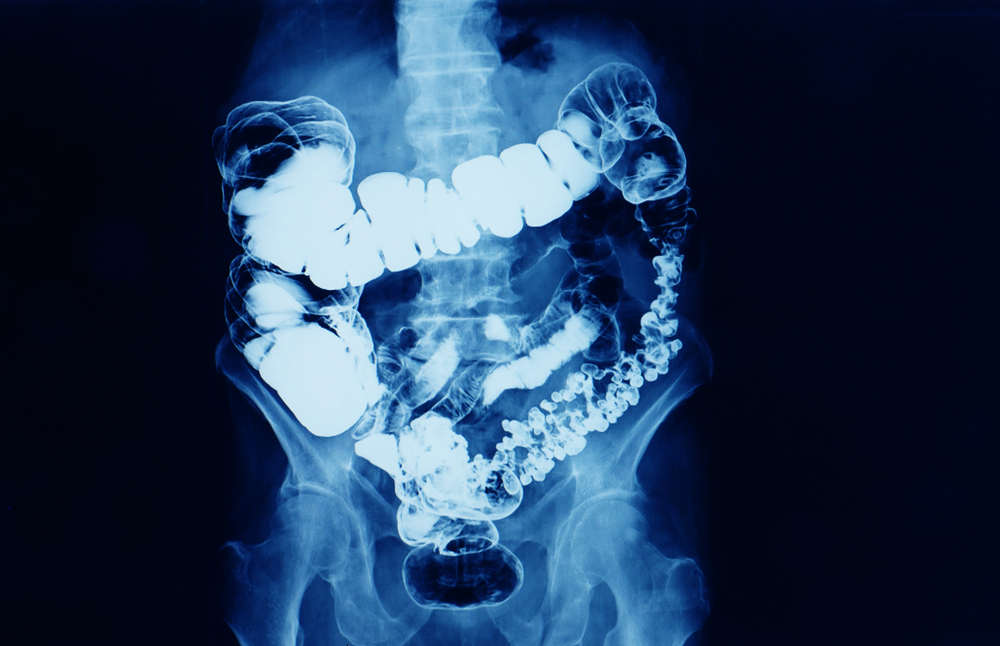

Bladder Cancer

Diagnosis involves imaging and cystoscopy. Treatment varies, including surgery, chemotherapy, immunotherapy, or a combination, depending on the cancer’s stage.